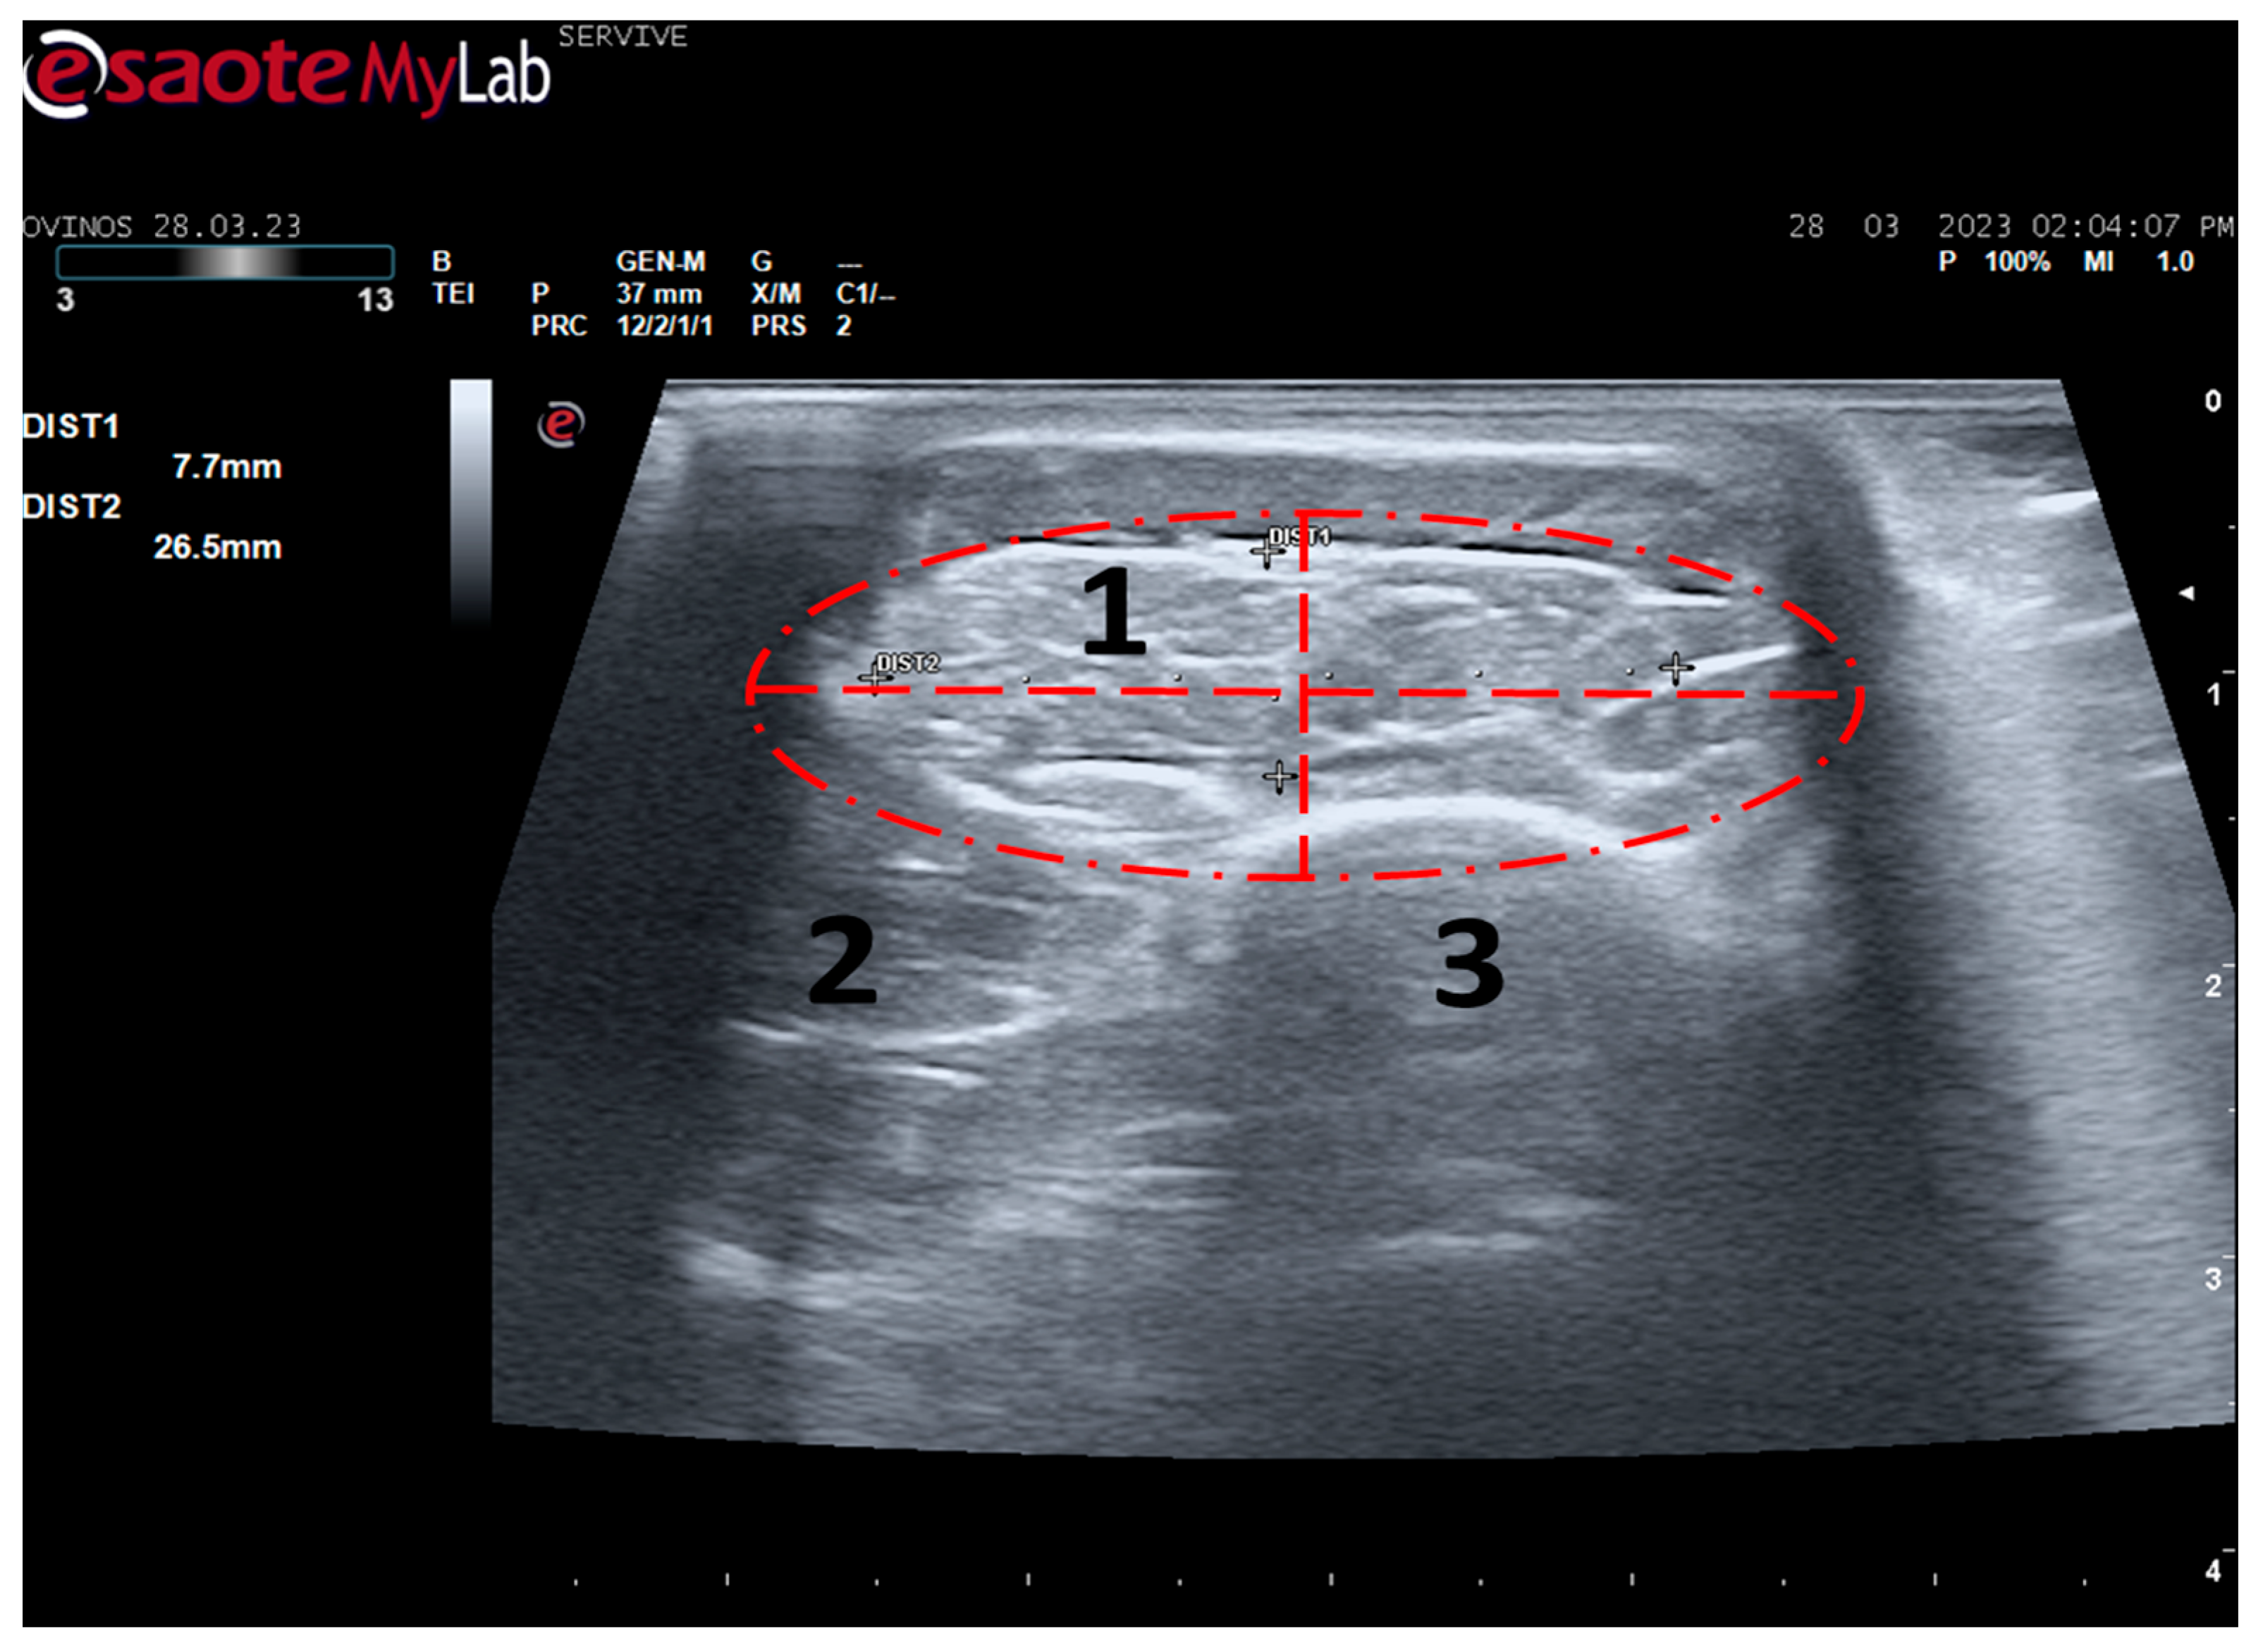

Figure 7.

Ultrasound image of the left cranial tibial muscle taken close to its origin, bounded by the red dashed circle. (1) Tibialis cranialis muscle; (2) extensor digitorum longus muscle; (3) tibia. DIST1 (vertical red dashed line) and DIST2 (horizontal red dashed line) represent the thickness and width of the muscle, respectively.

Tibialis cranialis muscle width and thickness were determined in triplicate at three different levels: close to its origin, in the middle of its muscle belly, and close to its insertion. The ultrasound appearance of the muscle is speckled due to the reflection of the perimysial connective tissue, which appears moderately echogenic and allows the fascial architecture of the muscle to be seen. The limits of the muscle are clearly visible since the epimysium that covers it is a very reflective structure (Figure 7). The muscle appears as the first muscle mass arising laterally to the crest of the tibia, occupying a craniolateral position in the leg, cranially to the tibia. The thickness and width values measured close to its origin, in the middle of its muscle belly, and close to its insertion can be found in Table 2. As expected, the dimensions of the muscle are greatest in the middle of the belly of the muscle, being smallest close to the insertion site on the tarsus and metatarsus, and presenting intermediate values at their origin in the lateral condyle of the tibia, lateral edge of the tibial tuberosity, and small surface on the lateral surface of the tibia.